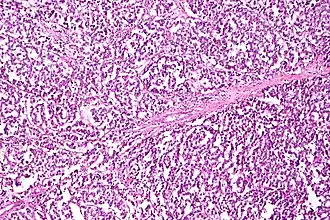

| Micrograph of a dysgerminoma, H&E stain. | |

They are exceptionally associated with hypercalcemia. On gross examination, dysgerminomas present with a smooth, bosselated (knobby) external surface, and are soft, fleshy and either cream-coloured, gray, pink or tan when cut. Microscopic examination typically reveals uniform cells that resemble primordial germ cells. Typically, the stroma contains lymphocytes and about 20% of patients have sarcoid-like granulomas. Metastases are most often present in the lymph nodes.